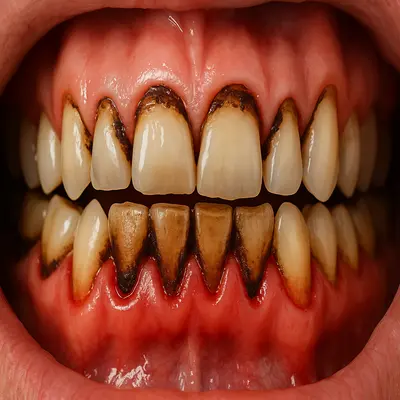

پوسیدگی دندان همراه با گیر کردن خوراکی شیرین بین شیار دندان و التهاب لثه

نمای نزدیک از پوسیدگی شدید دندان و ریشههای عصبی ملتهب در دهان انسان